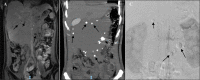

Intra-abdominal venous malformations and inferior vena cava aneurysms are rare and difficult to diagnose because of their nonspecific clinical symptoms. These vascular anomalies are important entities due to the risk of thrombosis or rupture. According to the classification of International Society for the Study of Vascular Anomalies, venous malformations are classified as low-flow vascular anomalies, showing absence of arterial and early venous enhancement and slow gradual filling with contrast on delayed venous imaging. Phleboliths related to thrombosis and calcifications, are the key finding of venous malformations. In this article, we report an exceptional case of large intra-abdominal venous malformations in associated with an inferior vena cava aneurysm.